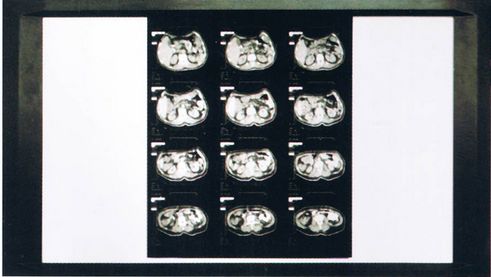

随着现代医学与高新技术的发展,放射科的影像阅读模式也在发生变化,许多大医院都开始逐步放弃使用医用观片灯而使用电脑显示器进行阅片,但是我国国情决定绝大多数基层医院仍将长期使用医用观片灯进行阅片。医用观片灯是直接获取数字影像照片诊断信息的器械,其性能的优劣将直接影像诊断质量。通过荧光灯观片灯和医用LED观片灯对临床病例的阅片效果进行了比较与分析,以评价两者的优劣。

随着计算机X线摄影(CR)、数字X摄影(DR)的应用与普及,医学影像学全 面进入了数字化时代。数字影像照片(激光照片)也逐步取代传统的模拟照片的使用。数字化激光打印图像是数字化照片图像的一种,由于它记录图像信息能力强,图像质量好,逐步成为影像胶片硬拷贝记录的主要方式,而数字影像照片的zui大密度值一般要求大于3.5以上,普通模拟照片的zui大密度值一般要求大于2.5,医用观片灯是直接获取数字影像照片诊断信息的器械,其性能的优劣直接影响诊断质量,因此对医用观片灯的要求也应该有相应的提高,以满足临床诊断的需求,保障诊断的质量。通过试验表明在普通荧光灯观片灯和LED观片灯下,临床病例的观察,效果相似。但传统的普通观片灯主要采用日光灯管,缺点较多,包括灯管寿命短,在观片区域容易产生暗区,易造成误诊;易闪烁对医生眼睛造成影响;耗能高等,而医用LED观片灯主要采用的是LED照明,体积小;驱动电压低、耗电量低、无闪烁、反应速率快、耐震性佳等优点。因此LED观片灯比普通观片灯更为适用。不仅能够显示更为丰富的影像层次,也能更有利于保护放射科医生的眼睛健康。